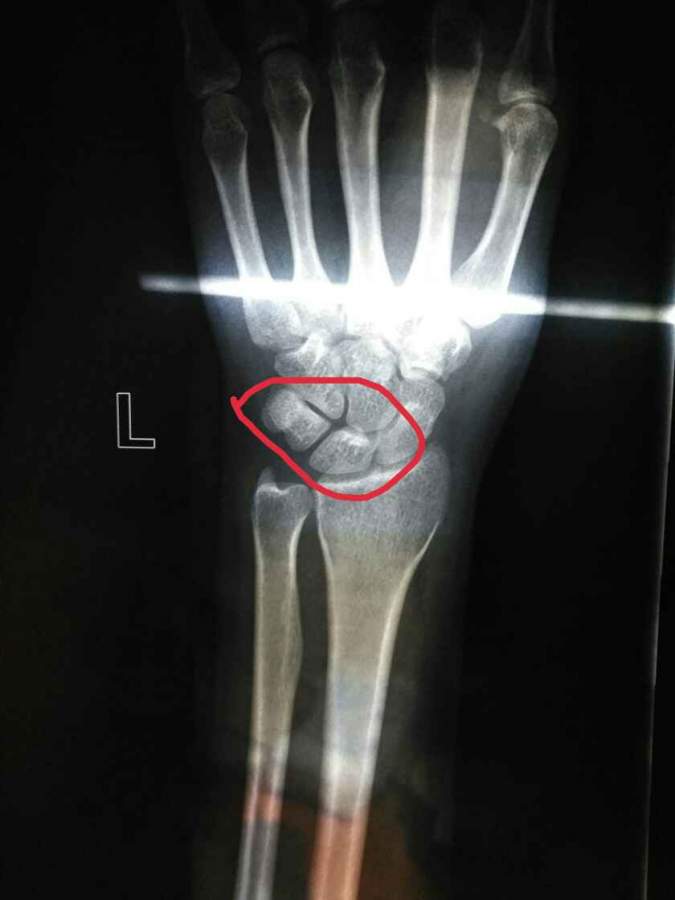

如题,能否帮我看一下图一手腕处的撕裂性骨折是指红线标记的位置吗?如果是的话,那图二算是恢复了吗? 发自小木虫Android客户端 |